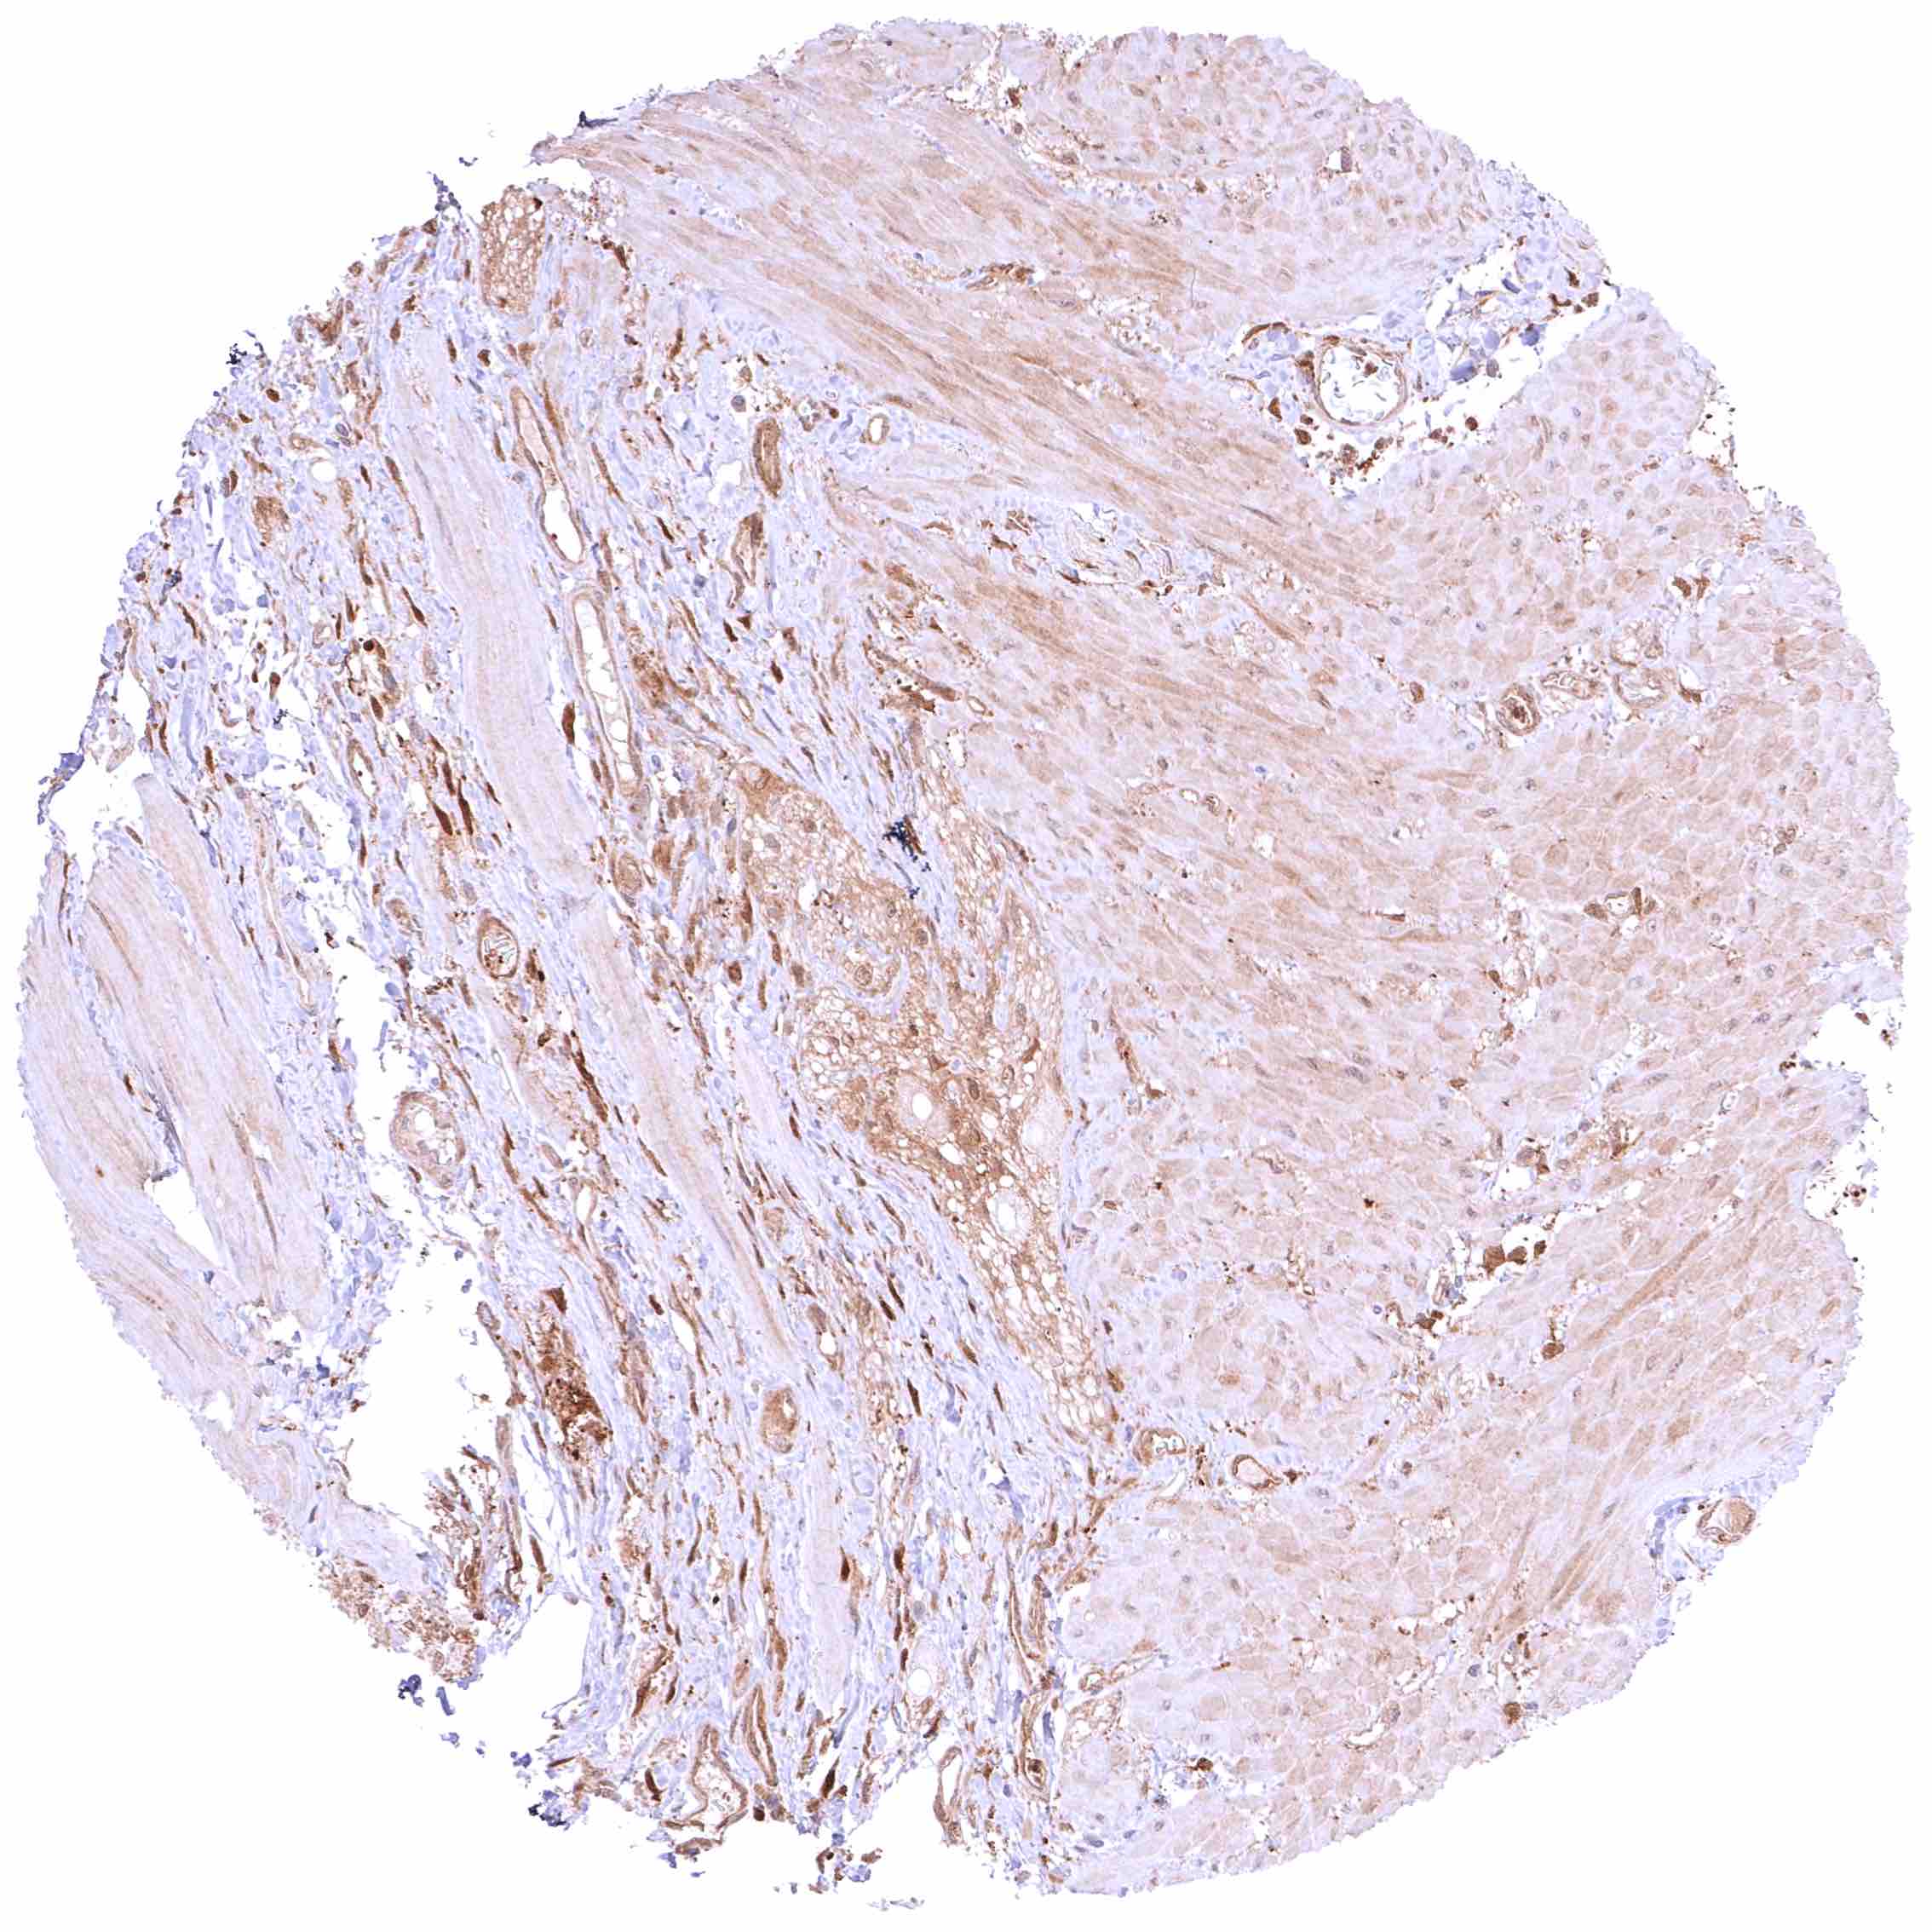

Uterus, myometrium – Distinct, nuclear and cytoplasmic GSTP1 positivity of muscle cells.